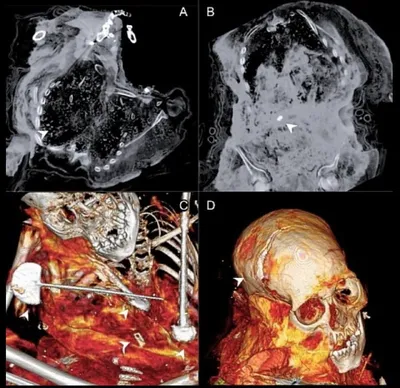

Мумии детей с вулканов Ампато и Сара-Сара. Международная команда учёных исследовала мумифицированные останки детей, обнаруженных ранее на склонах вулканов Ампато и Сара-Сара в Перу. При помощи компь